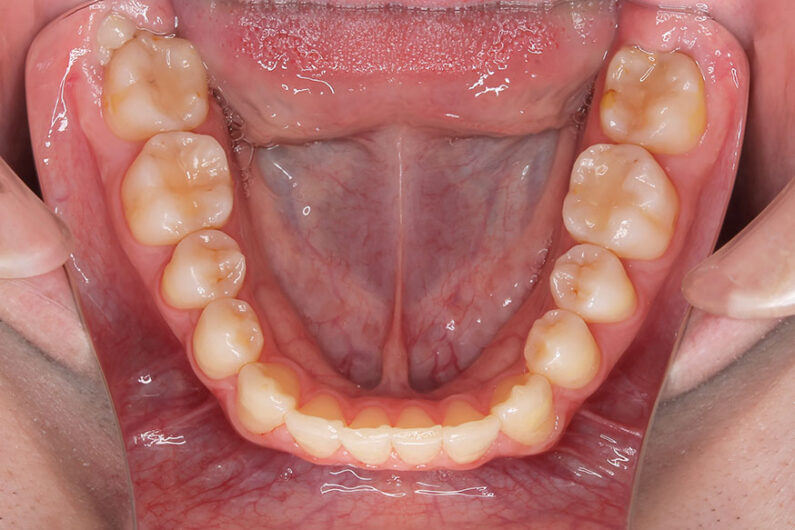

受け口を気にされ、他院からの紹介で来院された患者さんです。

小学2年生、生え変わりの時期から小児矯正を開始しました。

小児矯正で前歯の咬み合わせを改善し、

永久歯列完成後の中学生から非抜歯治療にて本格矯正を開始。

配列し仕上げました。

受け口の治療は、前歯の交換時期(小学校1年生ごろ)から小児矯正を始めることをお勧めします。

この時期に前歯の咬み合わせを治しておくことが後々重要になります。